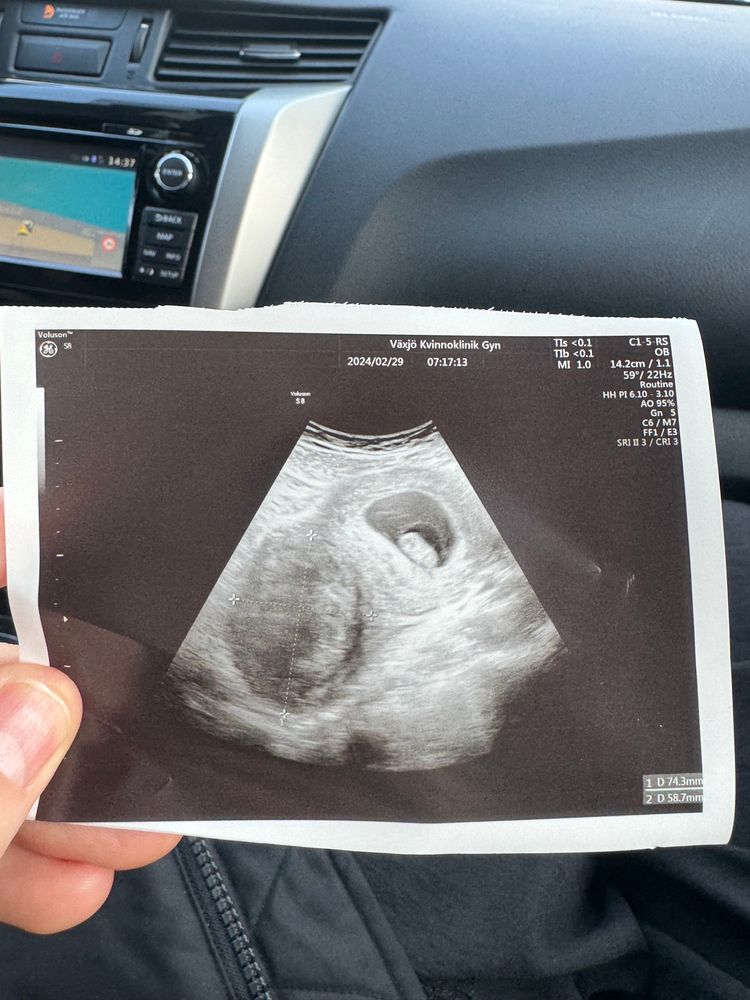

Изображение Это в понедельник Изображение Это сегодня

Anna, в понедельник точно двое, сегодня вроде один, либо прячется) но я не поняла… почему она сначала говорит что бьются сердца, а потом меняет мнение и говорит что один?😕

Деметра, спасибо!! Да да в понедельник она на старом аппарате и то увидела)) а тут на новом она не смогла найти))

Kuralay Kuanisheva, ещё больше запутали) оказывается новый аппарат не гарантия) если врач грамотный ,хоть на каком увидит)) ей сначала показались два ,второй за первым ,но потом сказала нет,что видит только одного ) Иду через неделю на узи и там уже будет точно понятно )

Софья, здравствуйте! В итоге один ) на узи в 8 и в 10 и вот в 12 недель одного видели . Только вот на 7 неделе два было и я вообще не знаю что это может ошибка какая-то))